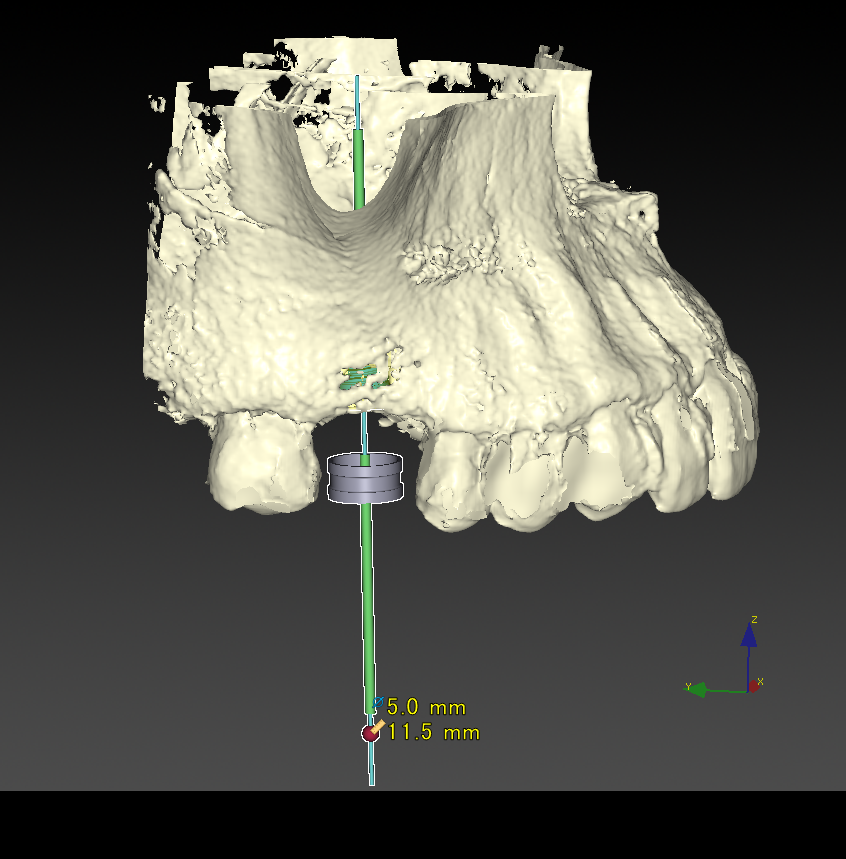

CTシミュレーション

CTデータをインプラント解析ソフトに入れ、手術のシミュレーションをします。

・骨の状態を確認し、骨造成が必要か見極めます。

・シミュレーションでインプラントが可能か確認し、インプラントのサイズを調べます。

埋入ガイド

CT画像上にて決定した埋入位置で製作された埋入ガイド。正確でスムーズな手術を行えます。